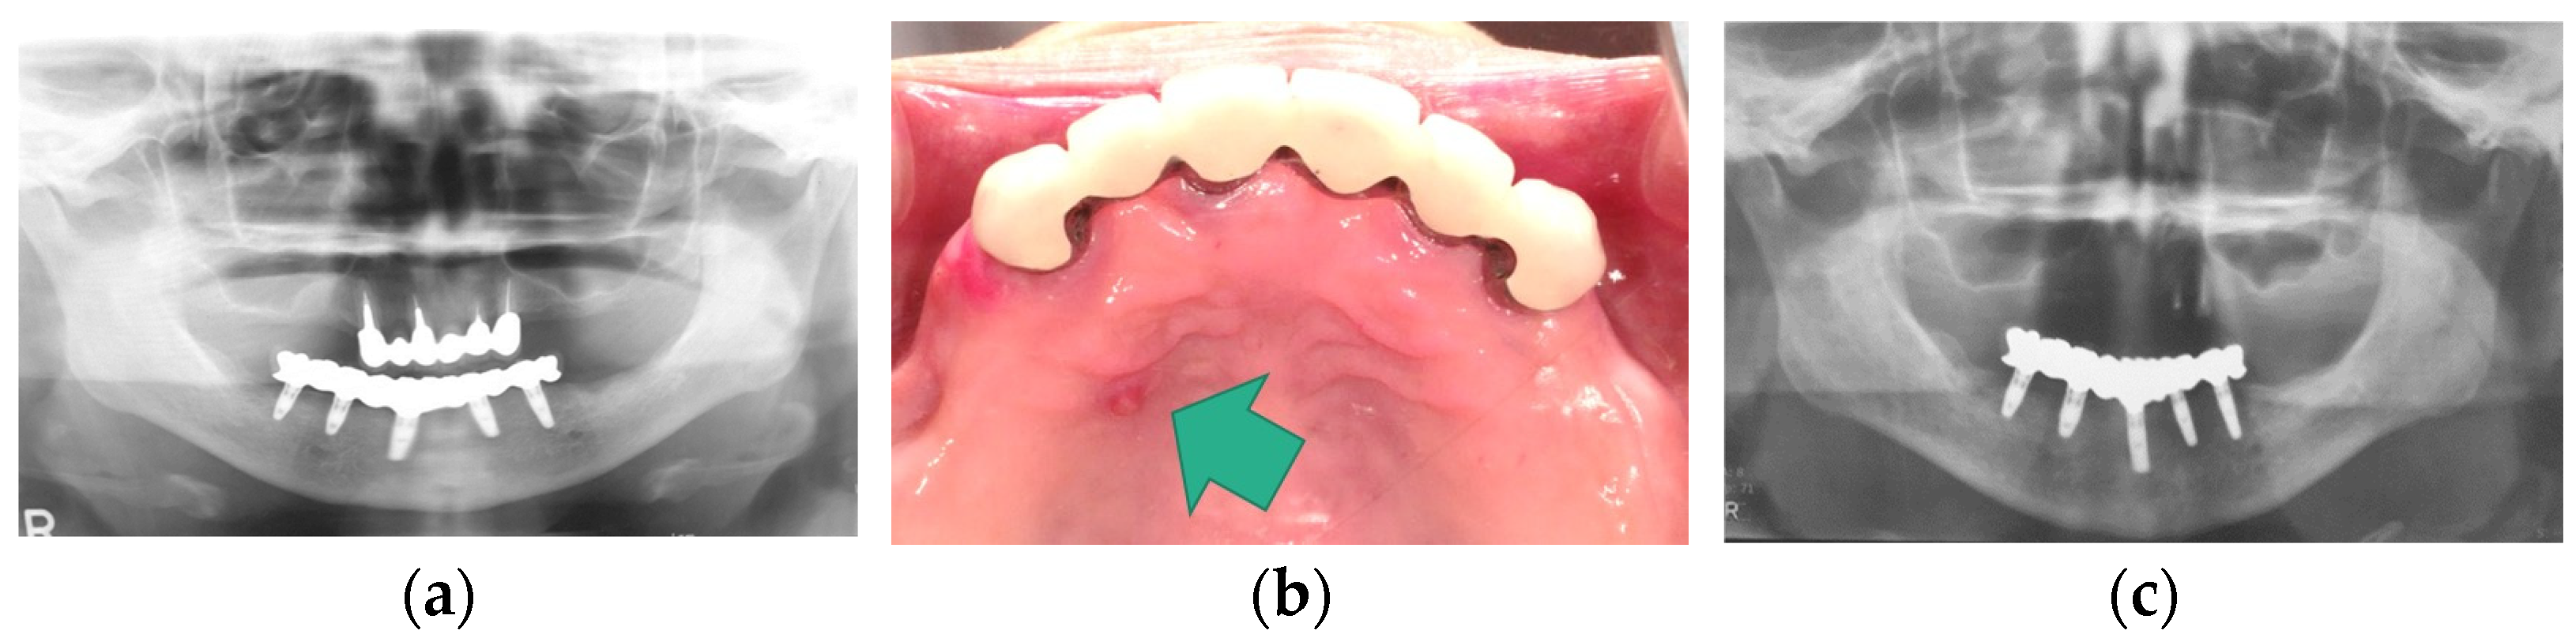

3.3.3. Implant Treatments for Anterior Hyperfunction and Combination Syndrome

Implant-supported prostheses can play a critical role in the rehabilitation of patients who have lost their teeth. In patients with anterior hyperfunction or combination syndrome, it is reasonable to understand that implant-supported prostheses can contribute to their rehabilitation. In these patients, implant-supported prostheses can work effectively from two viewpoints [19]:

• Provision of stable posterior occlusal supports by mandibular implant-supported prostheses;

• Provision of rigid prostheses in maxillary anterior region against anterior hyper function by maxillary implant-supported prostheses.

Although implant placement may be impossible due to the limitation of residual bone height and width in some cases, if delivered properly, implant-supported prostheses can lead to satisfactory results [8,15,17,19,28,29,30,31,32,33,34,35,36]. The reestablishment of posterior occlusal supports by implant-supported prostheses may contribute to the recovery of impaired maxillary anterior teeth by anterior hyperfunction. In addition, maxillary implant-supported prostheses opposed by the remaining mandibular anterior teeth reduce maxillary anterior and posterior alveolar bone loss compared with conventional dentures [37]. We have also experienced cases where implant-supported prostheses for patients with anterior hyperfunction contributed to the recovery of damaged maxillary anterior teeth (Figure 7).

However, there have been multiple reports that have presented mandibular implant-supported overdenture-induced anterior hyperfunction, subsequent bone resorption, and the formation of flabby hyperplastic tissues at the anterior site beneath maxillary complete denture base-opposing implants [38,39,40,41,42,43]. These reports suggested the risk of mandibular implant-supported overdentures for destructive changes on the maxillary anterior site. In fact, we experienced the negative effects of mandibular implant-supported overdentures on maxillary anterior sites and mandibular posterior sites (Figure 8). In addition, we also experienced a clinical case where a mandibular implant-supported fixed prosthesis in a patient with only maxillary anterior teeth worked as anterior hyperfunction and root fracture of the maxillary anterior tooth was confirmed. This patient’s case resulted in edentulous maxilla due to sequential root fracture and the patient was rehabilitated with maxillary complete denture, unfortunately (Figure 9). These findings suggest the risk of mandibular implant-supported prostheses working as anterior hyperfunction. Meanwhile, contrary to these reports, a recent systematic review and meta-analysis revealed that no significant difference was detected in maxillary anterior bone resorption between patients with mandibular two-implant-supported overdentures and with conventional mandibular complete dentures [18]. The retention mechanism (attachment types of overdentures), the relining of the maxillary complete denture, occlusal condition, and stages of edentulism might be associated with bone resorption, and the necessity of a well-designed randomized clinical study was suggested. However, it is important to note that mandibular implant-supported overdentures or mandibular implant-supported fixed prostheses as alternatives for conventional removable prostheses may make the problems complicated depending on the interventions.

Figure 7. Implant-supported prostheses for the patients with anterior hyperfunction: (a) pre-treatment; (b) post-treatment; (c) a panoramic X-ray image of post-treatment. Source: the authors.

Figure 8. Bone resorption in a patient with implant-supported overdenture: (a) a panoramic X-ray image at the delivery of overdenture; (b) a panoramic X-ray image at 19-year follow-up. Source: the authors.

Figure 9. Anterior hyperfunction by an implant-supported fixed prosthesis: (a) a panoramic X-ray image at the delivery of prosthesis; (b) fistula (green arrow) attributed to root fracture; (c) a panoramic X-ray image after the loss of maxillary anterior teeth due to anterior hyperfunction by mandibular implant-supported prosthesis. Source: the authors.